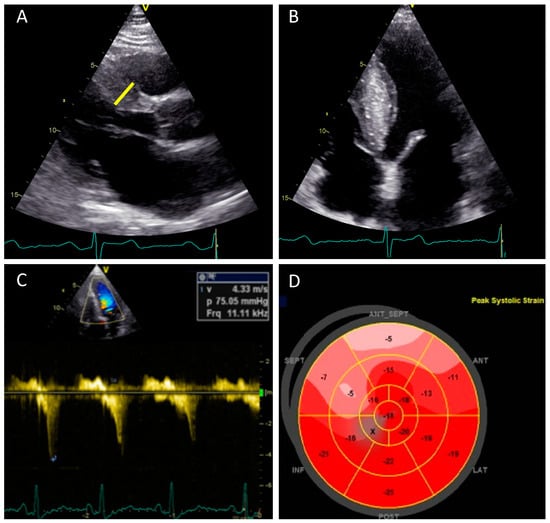

Diagnosis of HCM can be made in the majority of patients with two-dimensional transthoracic echocardiography (TTE) when an increased LV wall thickness >15 mm is detected with a nondilated cavity and in the absence of any other condition known to cause LVH of that magnitude (systemic hypertension or aortic stenosis) [6,116] (Figure 2A,B). In relatives of patients with HCM, documenting mild increases in LV wall thickness (12–14 mm) can be considered diagnostic. Increased right ventricle free wall thickness (>8 mm) is present in over one-third of patients with HCM [117]. Additional diagnostic criteria have been defined as septal to a posterior wall thickness ratio >1.3 in patients with normal blood pressure or septal to a posterior wall thickness ratio >1.5 in hypertensive patients [6,116]. Nevertheless, genotype-positive adults, including those who suddenly die, may have normal or near normal wall thickness [42]. It should be emphasized that asymmetrical LV hypertrophy is not pathognomonic of sarcomeric HCM, but it may be encountered in a variety of other congenital or acquired conditions like systemic hypertension, pulmonary hypertension, aortic stenosis, septal sarcomas, amyloidosis, Fabry disease, Friedrich ataxia, mucopolysaccharides, or glycogen storage disorders [118].

Closely related with SAM is mitral regurgitation (MR), which is usually functional in HCM and occurs as a result of SAM of the anterior leaflet, even if there are interindividual differences in the degree of MR for comparable degrees of SAM [122]. This variability occurs as a result of the mobility and length of the posterior mitral valve; a limited posterior leaflet excursion is associated with a more severe mitral regurgitation for the same degrees of SAM [123]. In most cases, MR due to SAM is directed posteriorly and is rarely severe. Another direction of the jet or a severe regurgitation should raise the suspicion of another associated mechanism, and transesophageal echocardiography (TEE) should be used along with TTE for clarifying the mechanism. In this case, intrinsic valvular abnormalities should be searched for such as: leaflet fibrosis, leaflet restriction secondary to “percussion injury” [124], a chordal rupture, or an associated myxomatous disease [125]. LVOT obstruction assessment at rest or during provocation results in a characteristic signal with a “dagger” shaped appearance showing late peaking flow in LVOT [126] (Figure 2C). Subaortic (i.e., LVOT) obstruction in HCM is due to SAM of the mitral valve contacting the ventricular septum in mid-systole. This creates mechanical impedance to blood flow as it exits the heart, resulting in a pressure gradient between the LV cavity and the aorta. Morphological features that contribute to the development of LVOT gradients are: narrowing of the outflow tract due to excessive thickening of the interventricular septum, apical displacement of papillary muscles, and elongated anterior leaflet of the mitral valve.

Significant impairment of longitudinal contractile function despite normal LVEF was demonstrated in a number of studies that showed abnormal reduced global longitudinal strain (GLS) values in HCM, but with preservation of basal to apical gradient (Figure 2D), an increase in circumferential strain, normal systolic twist or torsion, and reduction of untwisting in diastole [139]. In contrast, Reddy at al. reported systolic “paradoxical” lengthening in the longitudinal strain of the apical segments and attenuation of longitudinal strain values in the mid and distal segments of LV, findings that suggest a loss of base-to-apex gradient in the apical HCM form [126,140]. In one population of patients with nonobstructive HCM and no evidence of LVOT obstruction at baseline, higher GLS values (i.e., less negative) were associated with a greater likelihood of new or progressive heart failure [141]. However, the precise role of GLS in large populations of patients with HCM remains to be clarified.